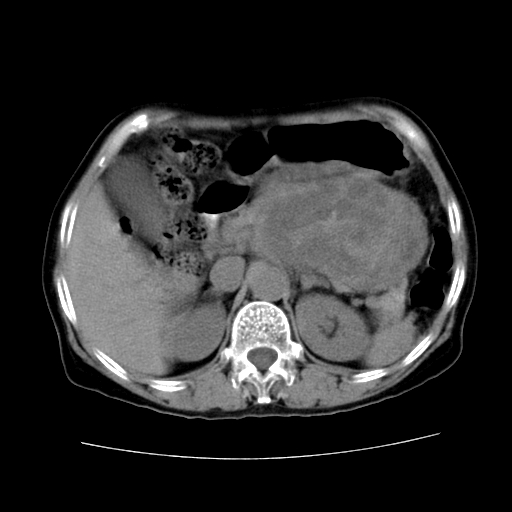

女性,72岁。

主诉中上腹部疼痛不适1年余。

胰腺尾部不规则巨大略低密度肿块,界限清楚,内密度不均,增强动脉期不均匀强化,门脉期明显退减并低于胰腺密度,肿瘤包埋于脾血管。多考虑;来源于胰腺尾部的“胰腺癌”。

考虑胰体尾部囊腺癌可能性大。肝右叶可疑转移.

该例有几个特点需注意:

1.肿瘤大而边界清

2.内部有钙化

3.强化时间较长

4.这么大的肿瘤对周围的血管无侵犯

以上几条均与胰腺癌不符

故考虑:胰岛细胞癌

1、这个病例确实有点难。影像主要显示胰腺体尾部占位,我们当初也是诊断胰体尾部囊腺癌可能性大,而且读片会上也很多人这么诊断的。

2、手术所见:打开腹腔发现胃与胰腺体尾部可见肿块,大小约10×8×11cm,质硬,不可推动,周围血供丰富。术中诊断:胃肿瘤侵及胰腺体尾部。

1)、胃小弯侧胃肠间质瘤(考虑恶性),瘤体大小13.5×7×6.5cm,上下切缘阴性。

2)、胃小弯1只、幽门下2只淋巴结慢性炎。免疫组化:cd117(+)、cd34(+)、sma(+)、desmin(-)、s-100(-)、ki-67<10%(+).

4、这个肿瘤太大了,而且密度不均性强化,从这点我们应该不能单纯诊断胰腺癌,而应想到目前流行的胃肠道间质瘤。这个肿瘤主要发生于胃壁浆膜层,所以显示与胃壁关系不是很紧密,故而大多认为是胰腺癌。